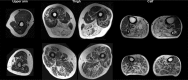

Spinobulbar muscular atrophy (SBMA) is caused by a trinucleotide repeat expansion in the androgen receptor gene on the X chromosome. There is a toxic effect of the mutant receptor on muscle and neurons resulting in muscle weakness and atrophy. The weakness can be explained by wasting due to loss of muscle cells, but it is unknown whether weakness also relates to poor muscle contractility of the remaining musculature. In this study, we investigated the muscle contractility in SBMA. We used stationary dynamometry and quantitative MRI to assess muscle strength and absolute and fat-free, cross-sectional areas. Specific muscle force (strength per cross-sectional area) and contractility (strength per fat-free cross-sectional area) were compared with healthy controls and their relation to walking distance and disease severity was investigated. Specific force was reduced by 14-49% in SBMA patients compared to healthy controls. Contractility was reduced by 22-39% in elbow flexion, knee extension, ankle dorsi- and plantarflexion in SBMA patients. The contractility decreased with increasing muscle fat content in muscles with affected contractility in SBMA. The decreased muscle contractility in SBMA may relate to motor neuron degeneration and changed fibre type distribution and muscle architecture.